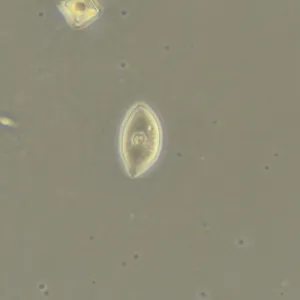

Фазово-контрастная микроскопия позволяет увидеть детали прозрачных образцов, которые практически не видны в светлом поле, и при этом не повреждать их окрашиванием. Метод применяют в разных сферах: медицине, биологии, ветеринарии, сельском хозяйстве, фармацевтике, экологии.